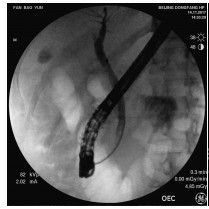

Endoscopic retrograde cholangiopancreatography combined with Spyglass in diagnosis of common bile duct papillary myxoma: A case report

Xuan DING, Linheng WANG, Gui JIANG, Yifei YUN, Xinyu LU, Yupu YAO

2021, 37(12): 2902-2904. DOI: 10.3969/j.issn.1001-5256.2021.12.034

Abstract(1315) HTML (221) PDF (2331KB)(47)

Abstract: